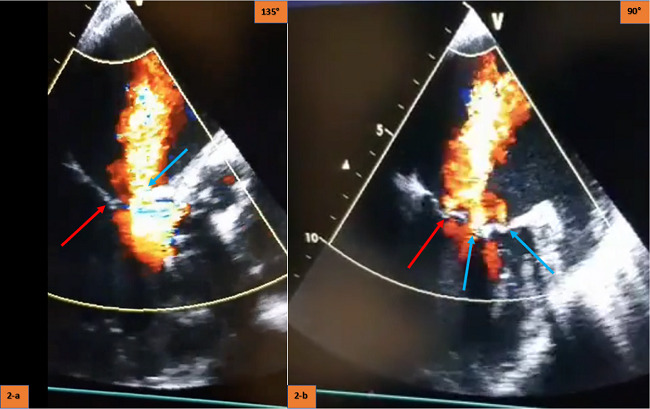

The patient was readmitted to our hospital with febrile sepsis two months after surgery. Jugular catheter infection was detected and blood culture identified Staphylococcus aureus as the pathogen. Echocardiographic evaluation of the patient did not changed during this period and did not suggest any signs of mechanical complication. Appropriate antibiotic therapy was applied and blood cultures were negative for infection. A permanent dual-chamber pacemaker was implanted, since a complete heart block occurred in this period. Furthermore, a permanent dialysis catheter was placed in the left jugular vein for the maintenance of dialysis. The patient was discharged in excellent health conditions, however, he was readmitted again with symptoms of dyspnea. Examination of the patient revealed apical systolic murmur and rales in breath sounds. There was no sign of infection or indication of biochemical markers six months after surgery. Transesophageal echocardiography showed obvious friction between the anterior mitral valve and the distal stent frame of the valve prosthesis and two different perforation holes of the anterior mitral valve (Figure 2, Videos 1 and 2). The degree of mitral regurgitation was rated as severe. Non-surgical management was decided due to EuroSCORE II of the patient (10.7%). The patient is currently monitored under stable conditions with dialysis treatment three times a week, avoiding volume overload.

So far, five similar cases have been published. Three of them reported mitral perforation as the underlying lesion, where infective endocarditis (IE) appears later on. The opposite chronology (IE causing mitral perforation) was suggested in the two other cases[3-5]. Our case included a duration related to sepsis, but mitral valve perforation without criteria for infection was detected six months later. The contribution of septicemia to the perforation process of anterior mitral valve as an erosive factor was not distinct. Besides, a paravalvular aortic leak had no contact with the mitral valve, resulting in endothelial erosion that predisposed to infective endocarditis. Our case contributes to the literature by revealing that deep transcatheter aortic prostheses implantation can lead to multiple perforations in the anterior mitral valve.